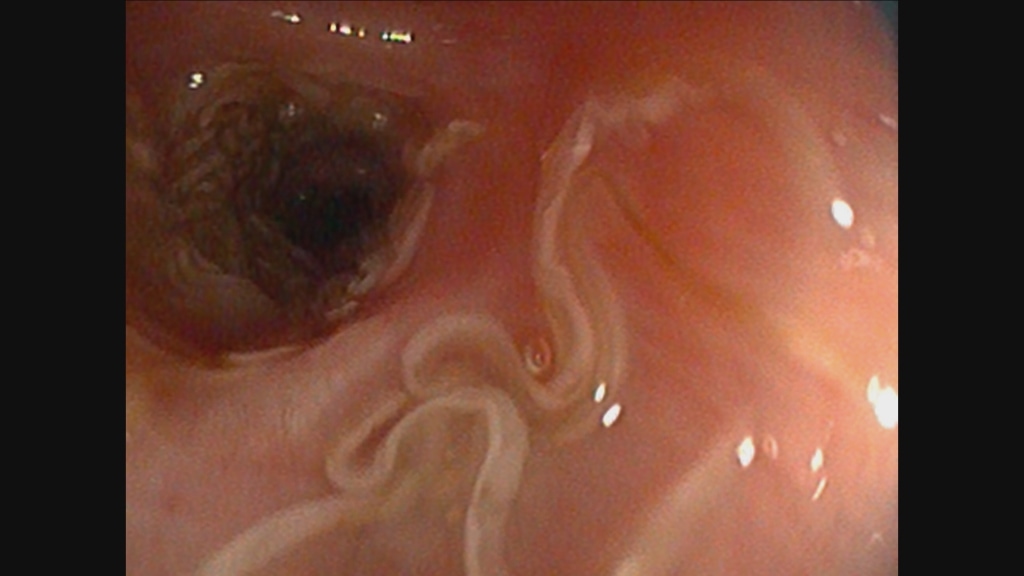

A graphic video taken by vets at one of the UK’s top animal hospitals has dramatically revealed the shocking cause of a dog’s constant cough.